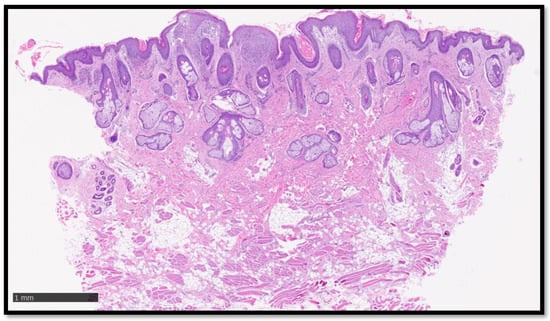

Cutaneous Sarcoidosis-like Eruption Following Second Dose of Moderna mRNA-1273 Vaccine: Case or Relationship?

Cazzato, G.; Ambrogio, F.; Foti, C.; Capuzzolo, M.; Trilli, I.; Casatta, N.; Lupo, C.; Carrieri, M.; Daini, D.; Colagrande, A.; et al. Cutaneous Sarcoidosis-like Eruption Following Second Dose of Moderna mRNA-1273 Vaccine: Case or Relationship? Diagnostics 2023, 13, 1286. https://doi.org/10.3390/diagnostics13071286